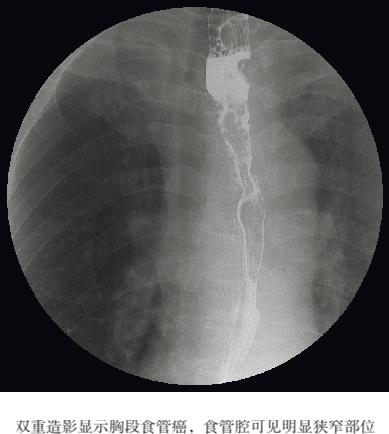

图2.2 双重造影(晚期食管癌)

根据其生长情况,晚期肿瘤会导致食管壁僵硬、正常黏膜结构被破坏、管腔内充盈缺损以及伴有近端扩张的狭窄。部分晚期肿瘤会出现沙漏状圆形狭窄,病灶边缘光滑,但浸润和溃疡不断增加,最终形成不规则轮廓(见图2.2)。